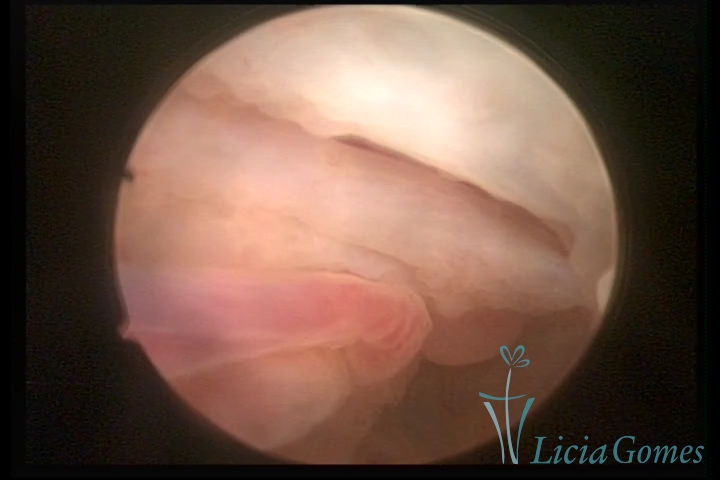

• Second part or middle section: the details of the buds are lost. It is possible to view longitudinal creases.